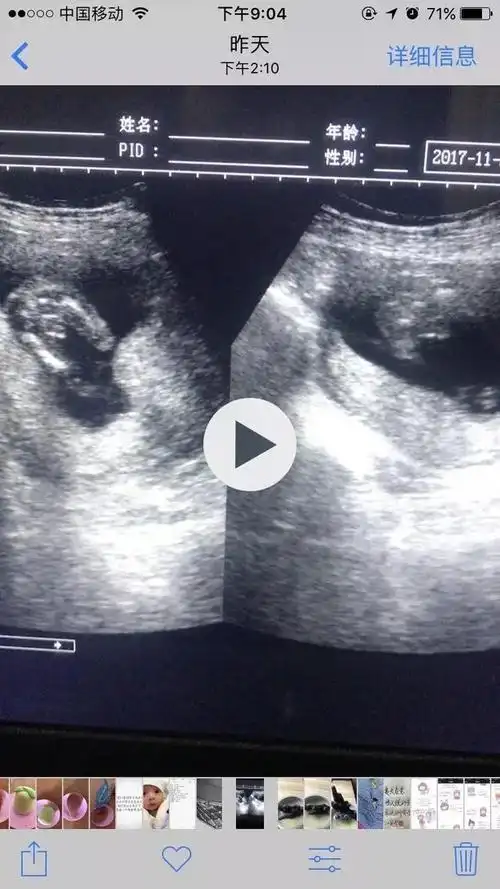

好幸运, 二胎16周就确定是男孩, 分享孕期自己的男宝症状

孕16周的胎儿有多大?宝妈应该注意些什么?育儿妈妈来支招